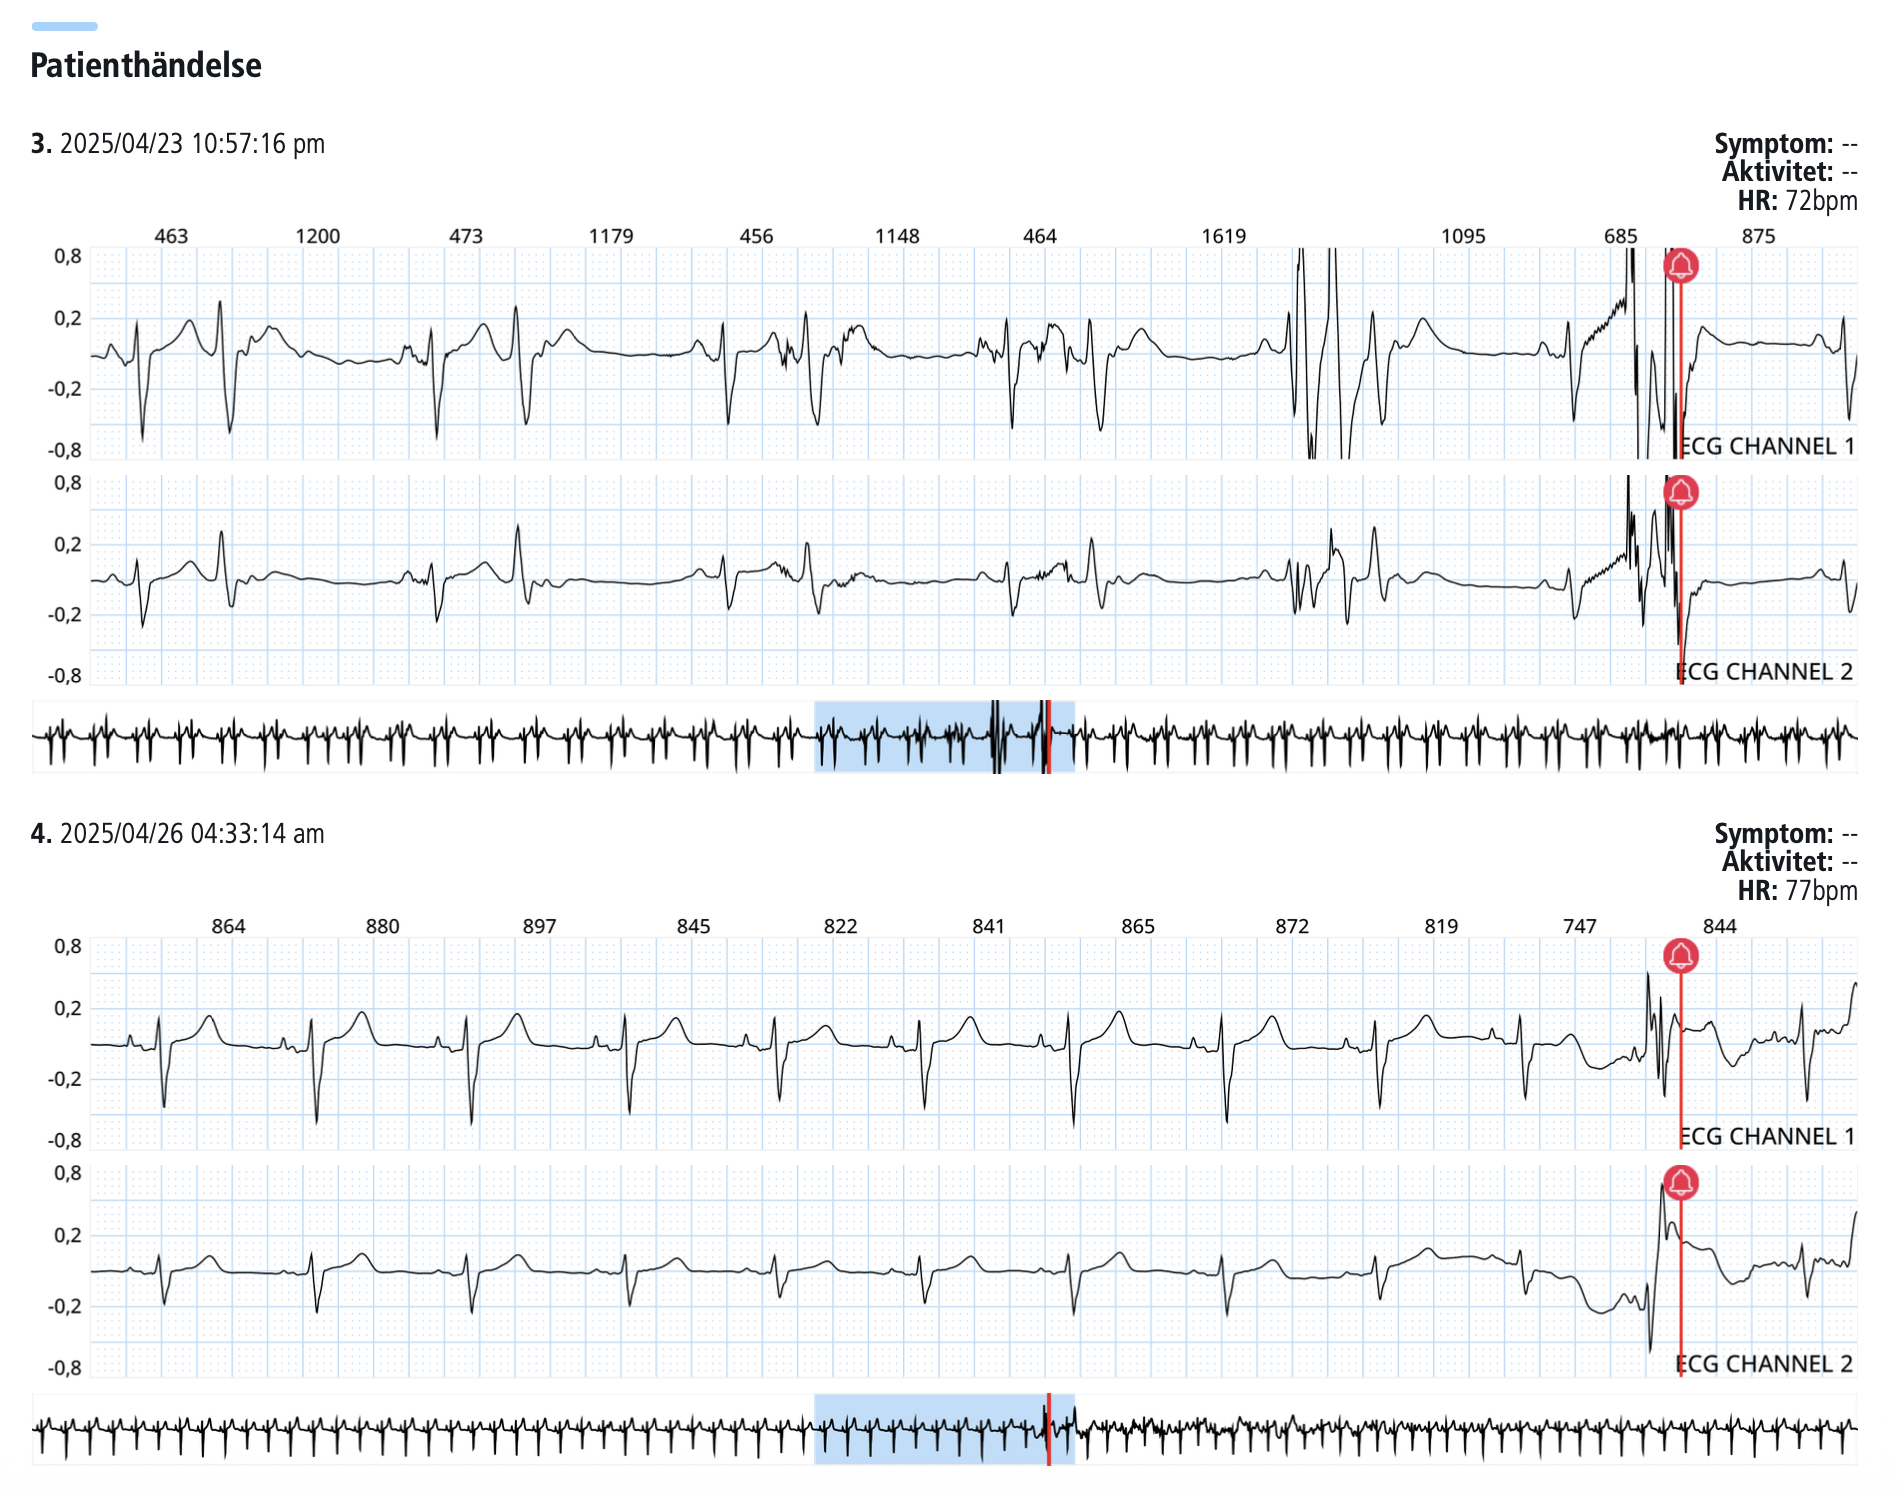

Patienthändelser

Här visas specifika händelser där hjärtats aktivitet analyseras i detalj, ofta kopplat till symtom eller avvikande rytm.